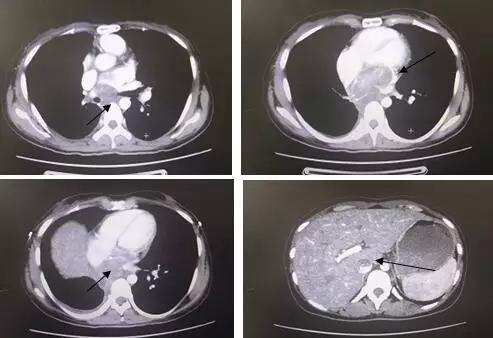

图为我院收治肺IMT患者复发后CT图像

我科于2012年9月收治一例肺部IMT患者,现将该病例进行分享。病例:冷×,女,26岁。因间断刺激性干咳半年,就诊于某医院,行肺CT示:右肺下叶支气管显示欠清,其内密度不均匀,远端近边缘处可见多个结节状、团块状钙化影,纵隔内未见明显肿大淋巴结。于2012年9月17日行“右肺下叶切除术”,术中见肿物位于右肺下叶,大小约10×8×8cm,肿瘤侵及膈肌、心包及食管,肺门淋巴结肿大。因肿瘤侵及下腔静脉无法完整切除肿瘤,在下腔静脉表面切除肿瘤,表面残留部分肿瘤组织,用电刀烧灼肿瘤组织。切除肿瘤侵及的部分膈肌,缝合膈肌。术后刺激性干咳症状缓解。术后病理报:[右肺下叶]炎症性肌纤维母细胞瘤,伴大面积玻璃样变性、钙化及骨化。肿瘤体积约7.5×7×5.5cm,多处神经可见肿瘤浸润,脉管未见肿瘤浸润,脏层胸膜及多处小支气管壁可见肿瘤浸润,支气管切缘及血管切缘未见肿瘤,周边肺组织淤血。分送(7组)淋巴结未见肿瘤转移(0/2)。免疫组化示:Ki-67(+10%),Vimentin(+),SMA(+),Actin(+),Desmin(-),CK(-)。术后25天就诊我科,复查肺CT示:右肺后下纵隔见不规则软组织肿块影,大小约为4.2×3.5×8.0cm,肿块明显强化,强化方式呈渐进性。肿块与心包界限不清,肿块向前压迫、侵犯下腔静脉。遂在我科行术后残余病灶区调强适形放疗。复查CT,肿瘤缩小,疗效评定为:PR。放疗后每隔3-6个月复查CT,病情稳定。放疗后3年,患者因呼吸困难再次就诊我科,行胸部增强CT示(2015年12月28日):纵隔7组可见肿大淋巴结,轴位短径约2.2cm。下腔静脉和左心房内增强扫描后可见充盈缺损,边界欠清,增强扫描静脉期可见不均匀轻度强化,强化程度与支气管残端肿物、7组淋巴结一致。影像诊断为:1.右肺下叶术后,支气管残端增厚伴软组织密度影,考虑术后复发。2.纵隔淋巴结转移。3.下腔静脉和左心房癌栓形成。外科认为无法行手术治疗,患者放弃治疗,回当地医院仅行对症治疗。